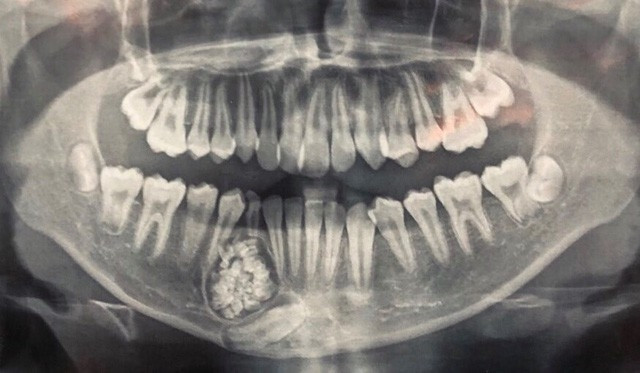

Bệnh viện Đa khoa tỉnh Khánh Hòa cho biết các bác sĩ vừa thực hiện ca phẫu thuật, lấy ra gần 100 cái răng trong khối u hàm dưới của 1 bệnh nhân 13 tuổi.

Ngày 15/6, bác sĩ Nguyễn Đức Tuấn, Trưởng khoa Răng Hàm Mặt, Bệnh viện Đa khoa tỉnh Khánh Hòa cho biết, các bác sĩ của đơn vị này đã tiếp nhận bệnh nhi H.G.K 13 tuổi đến khám răng tại bệnh viện. Tại đây, qua thăm khám, các bác sĩ đã phát hiện hàm dưới của bệnh nhi có 1 khối u răng ở xương hàm dưới.

Với sự phối hợp của Bệnh viên Răng Hàm Mặt Trung ương TP.HCM, các bác sĩ tại đây đã tiến hành phẫu thuật, lấy ra gần 100 cái răng trong khối u. Tất cả đều là những chiếc răng nhỏ li ti nhưng có đủ thân, tủy và chân răng.

Trước đó, bệnh nhân K. được người nhà đưa đến Bệnh viện Đa khoa tỉnh Khánh Hòa khám, thực hiện chỉnh hình răng mọc lệch và chậm thay răng mới. Qua chụp X-quang, các bác sĩ phát hiện một khối u răng ở xương hàm dưới.

Theo bác sĩ Nguyễn Đức Tuấn, u răng (hay còn gọi Odontoma) là một trong những loại u lành tính. U răng rất khó phát hiện, chỉ qua phim chụp X-quang mới có thể nhìn thấy.